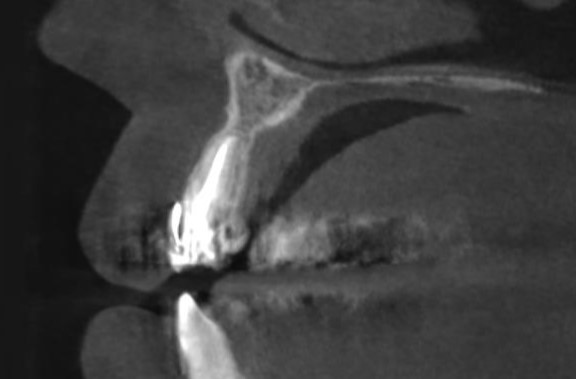

Киста в области зуба 2.2